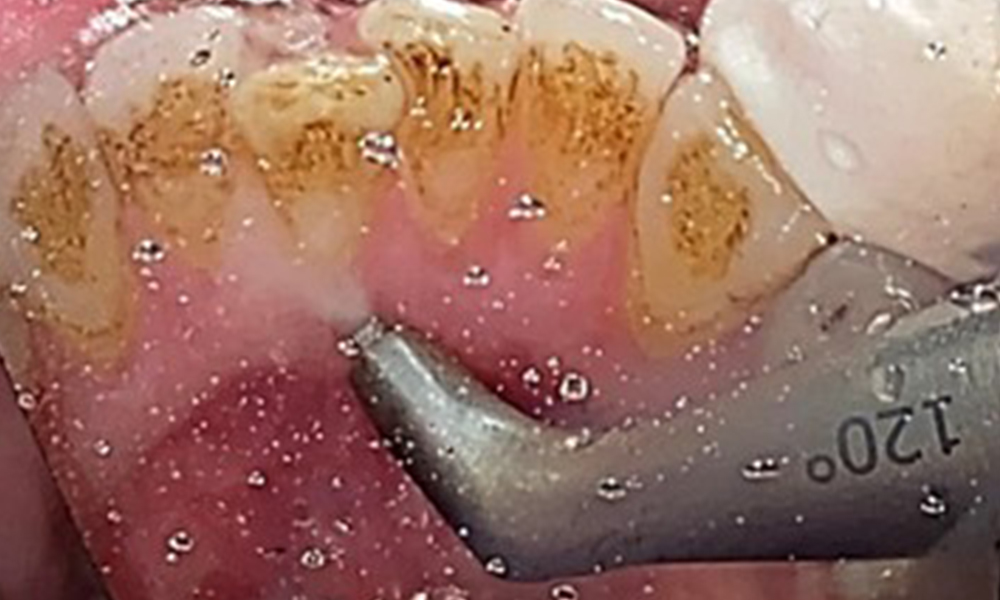

Instruction and motivation are important components of these appointments. Good home-based intraoral hygiene behaviour and understanding are important for patients. Plaque accumulation is particularly evident in the cervical regions (Fig. 8).

The objective would be to control disease risk by removing supragingival and subgingival biofilm. The instruments can be selected based on patient needs. First, calculus and any concretions must be removed using ultrasonic and/or manual instruments (Fig. 10).